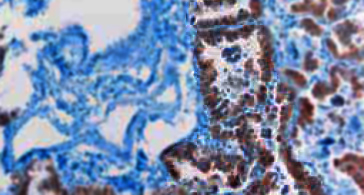

A small group of patients with non–small-cell lung cancer have genetic lesions that activate anaplastic lymphoma kinase (ALK). Crizotinib, an orally bioavailable ALK inhibitor, produced a 57% response rate in this subgroup, with mild grade 1 or 2 toxic effects.